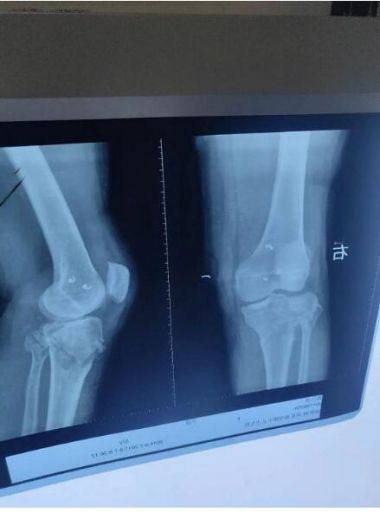

勾宪伟,男,15岁,沛县杨屯镇甘庄村。随父母在上海打工,玩耍时不慎摔伤右膝关节。即在上海中医院就医,x光片显示右胫骨髁间隆突撕脱性且移位骨折,院方的处理方案,必须动手术,用螺丝钉在内部固定,石膏外固定。由于手术费用过高,当时,家庭条件差难以承受,于是决定回老家沛县治疗。

生院长仔细看过x片后说:“这种骨折很好治。”听到生院长对儿子的骨折治疗十分有把握,担心害怕的父母才放下了心。

于是,生院长对骨伤开始进行诊断治疗:让患者平躺在治疗床上,要助手按住两腋下,并告知按得力度和角度,生院长用一只手握住患者踝关节上,另一只手扶着膝盖,连做两次伸曲膝关节的动作,手到骨正,随后外敷祖传正骨膏药,叮嘱患者可以做自由伸曲活动。原本不动就疼痛难忍,现通过生大夫正骨术后不仅不疼还可以伸曲自如,高兴的父母连连称赞生大夫神奇的正骨技术。